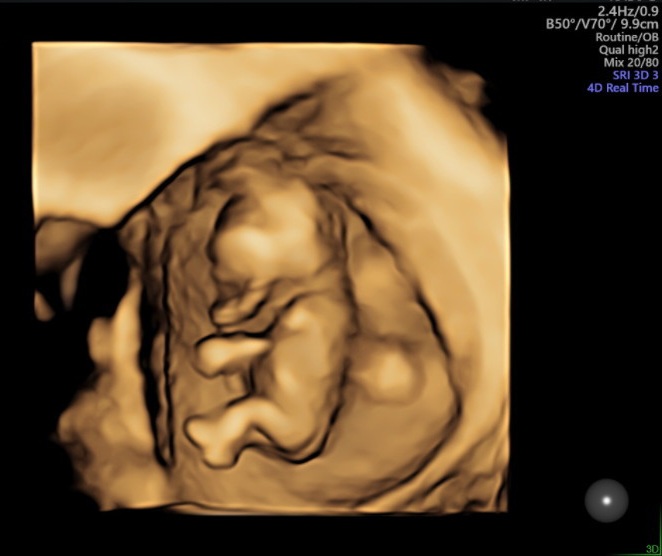

12주 정밀 초음파

젤리곰 탱이를 볼 수 있어요

아기 사이즈 및 기형아 체크

손, 발 길이 등등

자세하게 하나하나 체크하면서

초음파를 보기 때문에 약 40분가량 걸렸어요

양수량이 적당한지

아이가 잘 있는지 등등 체크하는데

화면으로 보는데 너무 신기하더라고요

저렇게 작은데 손, 발이 다 있다니...

울트라사운드라 아이가 초음파 하는데

움직이는 모습도 볼 수 있었어요

이렇게 3d 형태로 아기를 볼 수도 있어서

너무 신기하더라고요

제대로 된 초음파를 처음 해서 신기한 건지

아이가 있다는 게 신기한 건지

남편도 신기해서 계속 사진 찍으며

감탄하기 바쁘더라구요